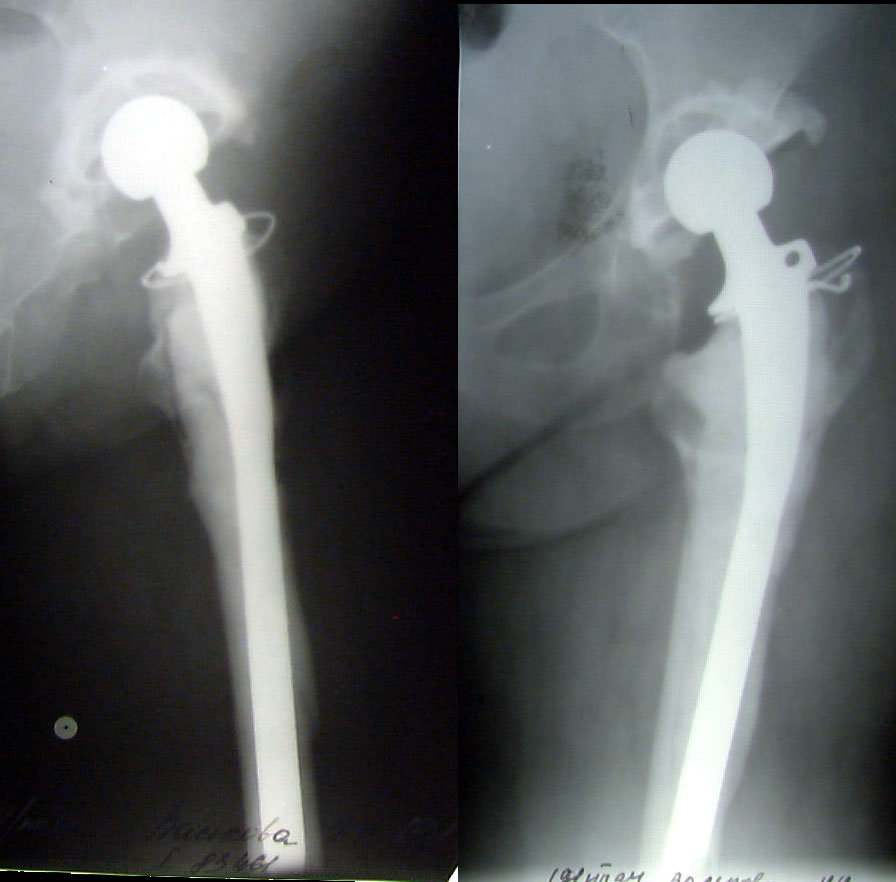

ÊÎÑÒÍÎÏËÀÑÒÈ×ÅÑÊÎÅ ÓÊÐÅÏËÅÍÈÅ ÂÅÐÒËÓÆÍÎÉ ÂÏÀÄÈÍÛ ÏÐÈ ÒÎÒÀËÜÍÎÌ ÝÍÄÎÏÐÎÒÅÇÈÐÎÂÀÍÈÈ ÏÎ ÏÎÂÎÄÓ ÄÈÑÏËÀÑÒÈ×ÅÑÊÎÃÎ ÊÎÊÑÀÐÒÐÎÇÀ ÊÎÑÒÍÎÏËÀÑÒÈ×ÅÑÊÎÅ ÓÊÐÅÏËÅÍÈÅ ÂÅÐÒËÓÆÍÎÉ ÂÏÀÄÈÍÛ ÏÐÈ ÒÎÒÀËÜÍÎÌ ÝÍÄÎÏÐÎÒÅÇÈÐÎÂÀÍÈÈ ÏÎ ÏÎÂÎÄÓ ÄÈÑÏËÀÑÒÈ×ÅÑÊÎÃÎ ÊÎÊÑÀÐÒÐÎÇÀ Âîëîøèí Â.Ï., Ìàðòûíåíêî Ä.Â., ÌÎÍÈÊÈ, Ìîñêâà, Ðîññèÿ

Êàðòèíêà Êàðòèíêà

ÝÍÄÎÏÐÎÒÅÇÈÐÎÂÀÍÈÅ ÏÐÈ Ò߯¨ËÛÕ ÔÎÐÌÀÕ ÏÀÒÎËÎÃÈÈ  ÒÀÇÎÁÅÄÐÅÍÍÎÃÎ ÑÓÑÒÀÂÀ ÝÍÄÎÏÐÎÒÅÇÈÐÎÂÀÍÈÅ ÏÐÈ Ò߯¨ËÛÕ ÔÎÐÌÀÕ ÏÀÒÎËÎÃÈÈ ÒÀÇÎÁÅÄÐÅÍÍÎÃÎ ÑÓÑÒÀÂÀ Õ.Ç.Ãàôàðîâ, È.À.Âàëååâ, À.Ð.Ñàãäåàâ, À.Ø.Ôàéçååâ, ÍÈÖÒ ÂÒÎ, Êàçàíü, Ðîññèÿ